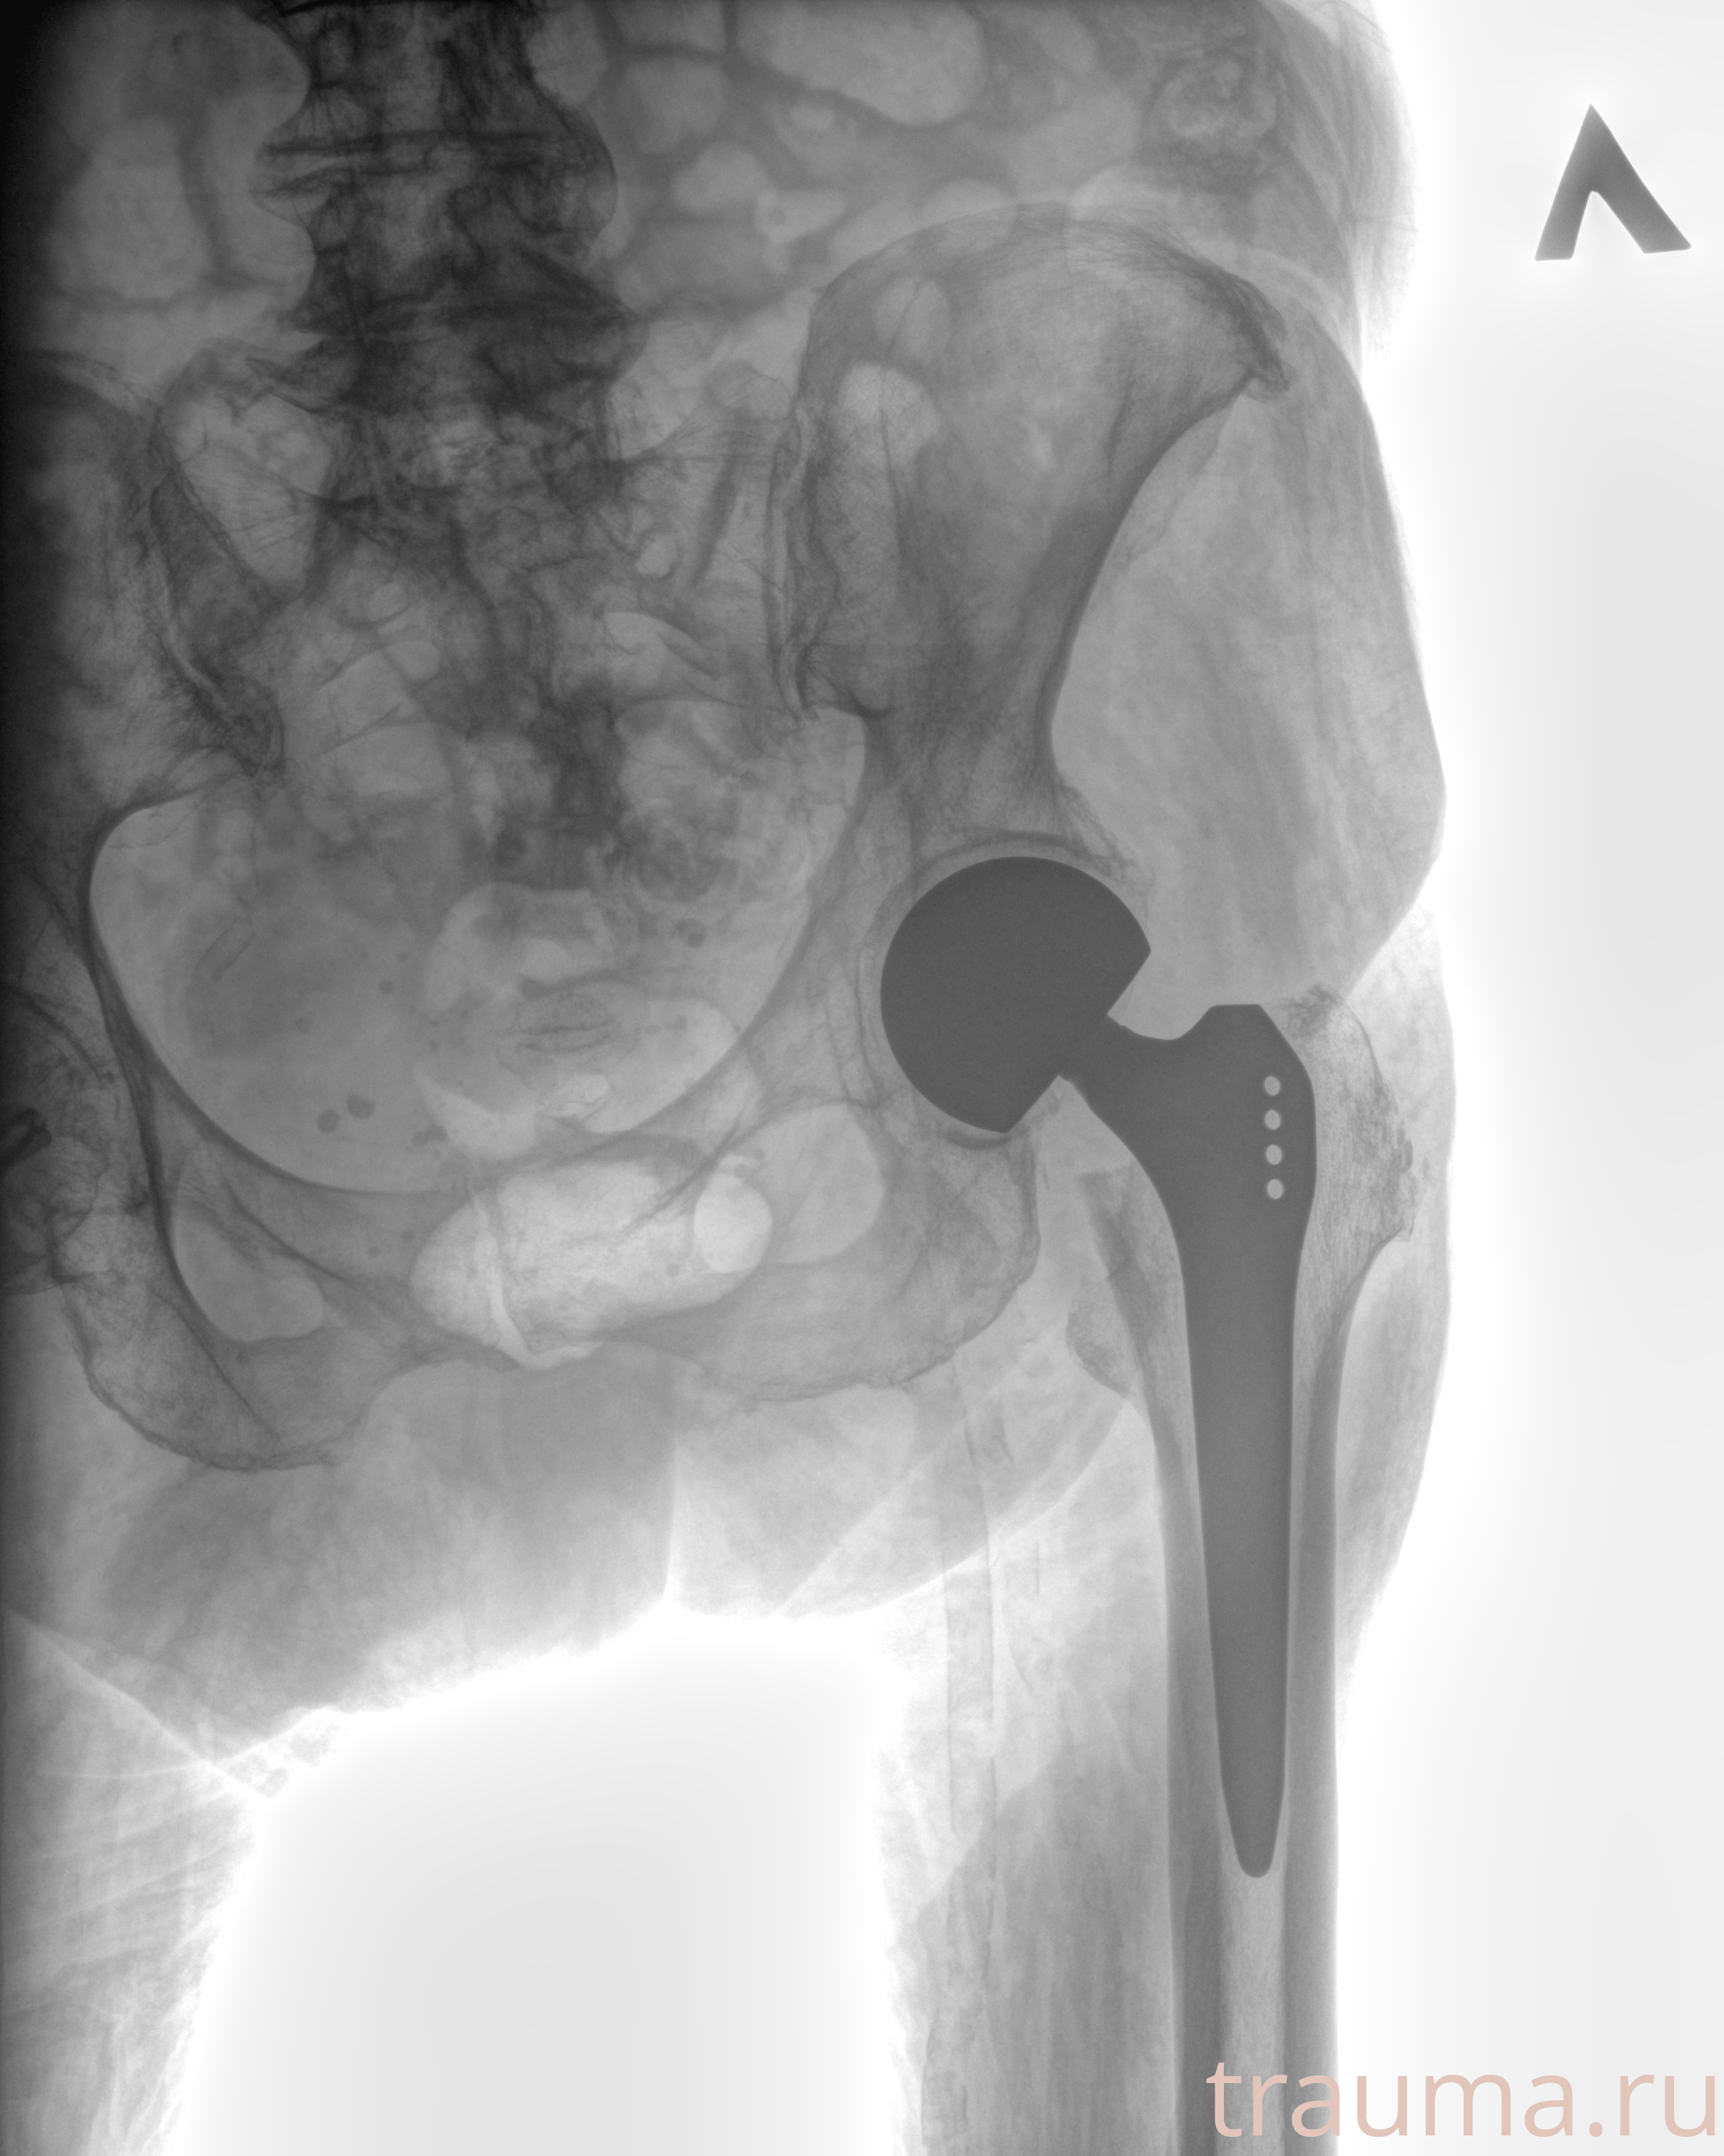

Рентген на дому: по вашему адресу приезжает врач-рентгенолог, травматолог-ортопед с мобильным рентгеновским аппаратом, проводит диагностику травмы или заболевания, делает необходимые рентгенограммы, дает рекомендации по дальнейшему лечению. Получить качественные снимки в домашних условиях возможно благодаря уникальной методике, разработанной МосРентген Центром для института  Склифосовского